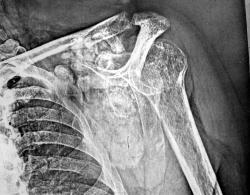

Архив. Припухлость в области плеча слева около года. Снимок единственный. Ваше мнение?

Больше беспокоит деформация сустава, боли малой интенсивности, температуры нет.

Хондроматоз?

Остеохондрома по медиально-внутренней поверхности лопатки....лет 20 назад попадалась такая, только раза в пять поменьше...все ребра напротив "истерла"...

Остеома, оссифицированная гематома

Может все просто - обызествленные л\узлы....как следствие перенесеного ранее подмышечного лимфангоита...

При операции большая опухоль между внутренней поверхностью лопатки и ребрами. Гистология - хондросаркома. Включения извести - обызвествление матрикса опухоли.